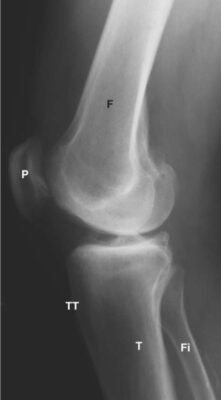

LIÊN HỆ X QUANG KHỚP GỐI

Ghi chú viết tắt:

- F = Femur; Xương đùi

T = Tibia; Xương chày - P = Patella; Xương bánh chè

- Fi = Fibula; Xương mác

- MFC = Medial femoral condyle ; Lồi cầu trong xương đùi

- TT = Tibial tubercle; lồi củ xương chày

- FT = Femoral trochlear groove; rãnh ròng rọc xương đùi

- A = Anterior cruciate ligament; ACL, dây chằng chéo trước

- B = Posterior cruciate ligament; PCL, dây chằng chéo sau